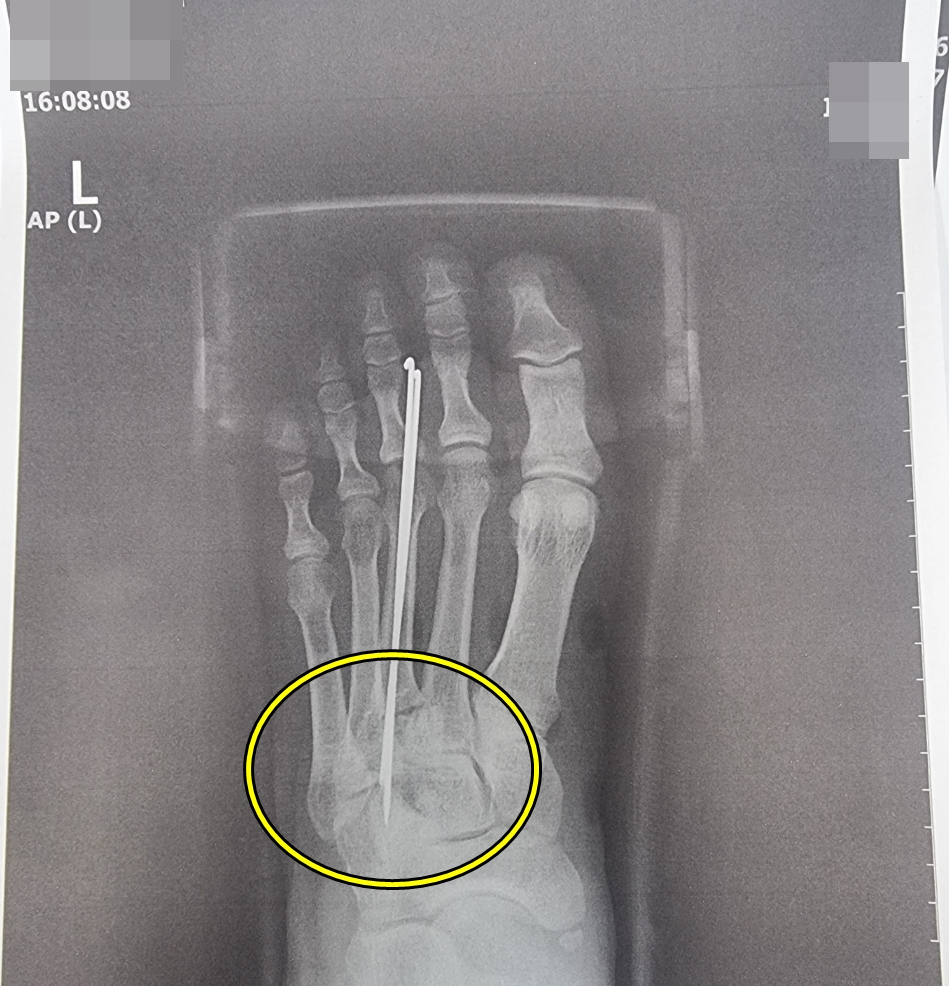

교통사고로 발등 부위에 중족골이 골절(5주 진단) 되어 금속물 삽입술을 시행으로 약 한 달간 입원치료를 받고 이후 통원치료를 하면서 금속물도 제거하는 등의 치료를 받았습니다.